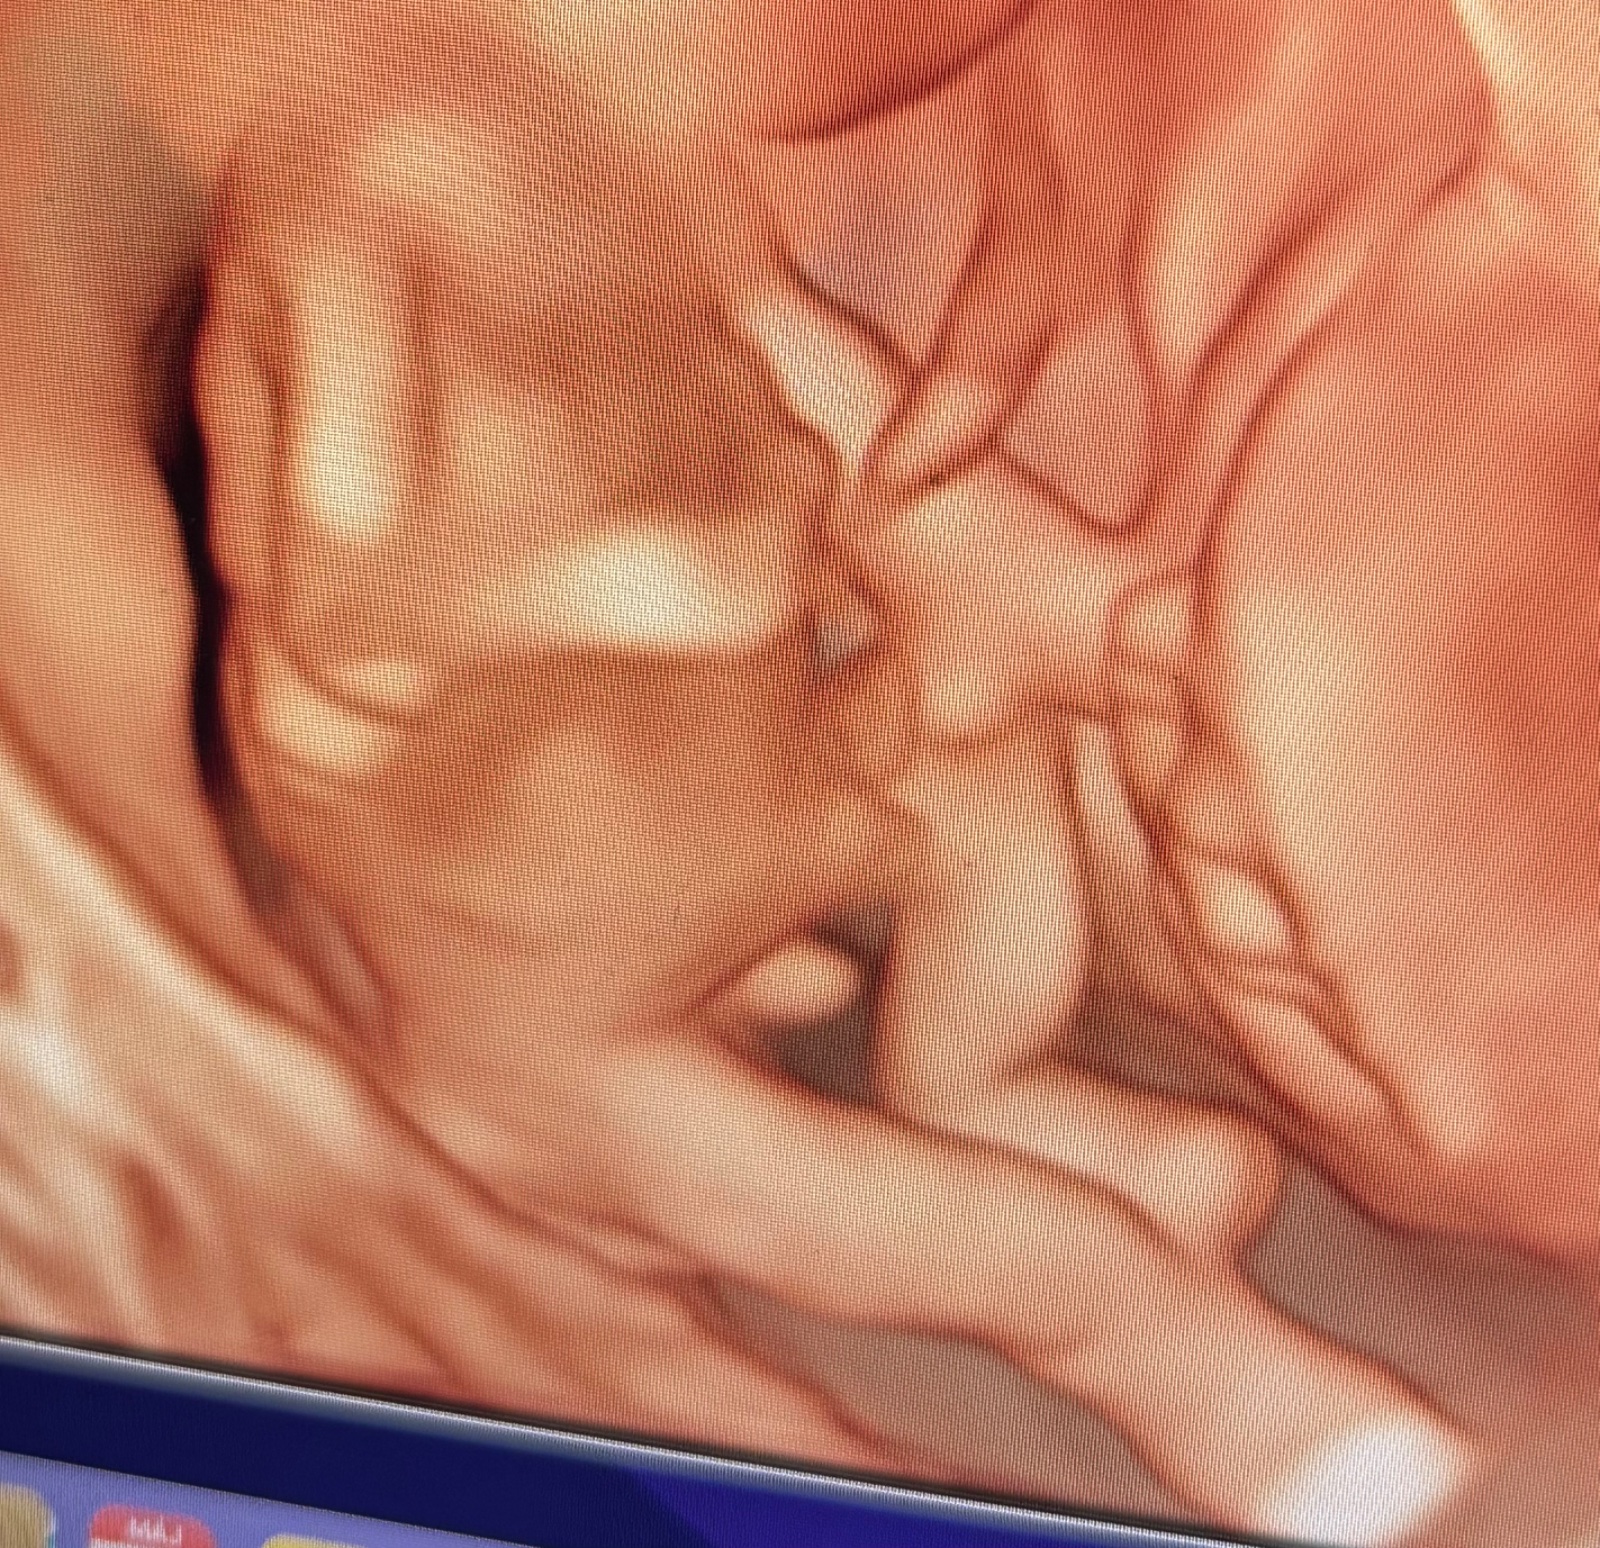

Jasné pohlavie dieťatka na 3D fotke v 15. týždni

@tanuuulka toto je tiež moje tretie dieťa a tiež dve predtým sa trafil v cca rovnakom týždni, takže dôverujem mu, mam vela fotiek aj videí z iného uhla kde je vidno, že to je chlapec, aj 2D😀 len ja tomu akosi neviem uveriť aj keď som odzačiatku cítila/vedela, že to bude chlapec..🙊😀

@vanilkovazmrzka jasnejší ultrazvuk už asi byť nemôže, len som odrezala hlavičku ☺️

@oliviakatka toto pohlavný výbežok už nie je, ako píšem, je to z 15 týždňa kedy už sú pohlavné orgány v podstate dovyvíjané 😊